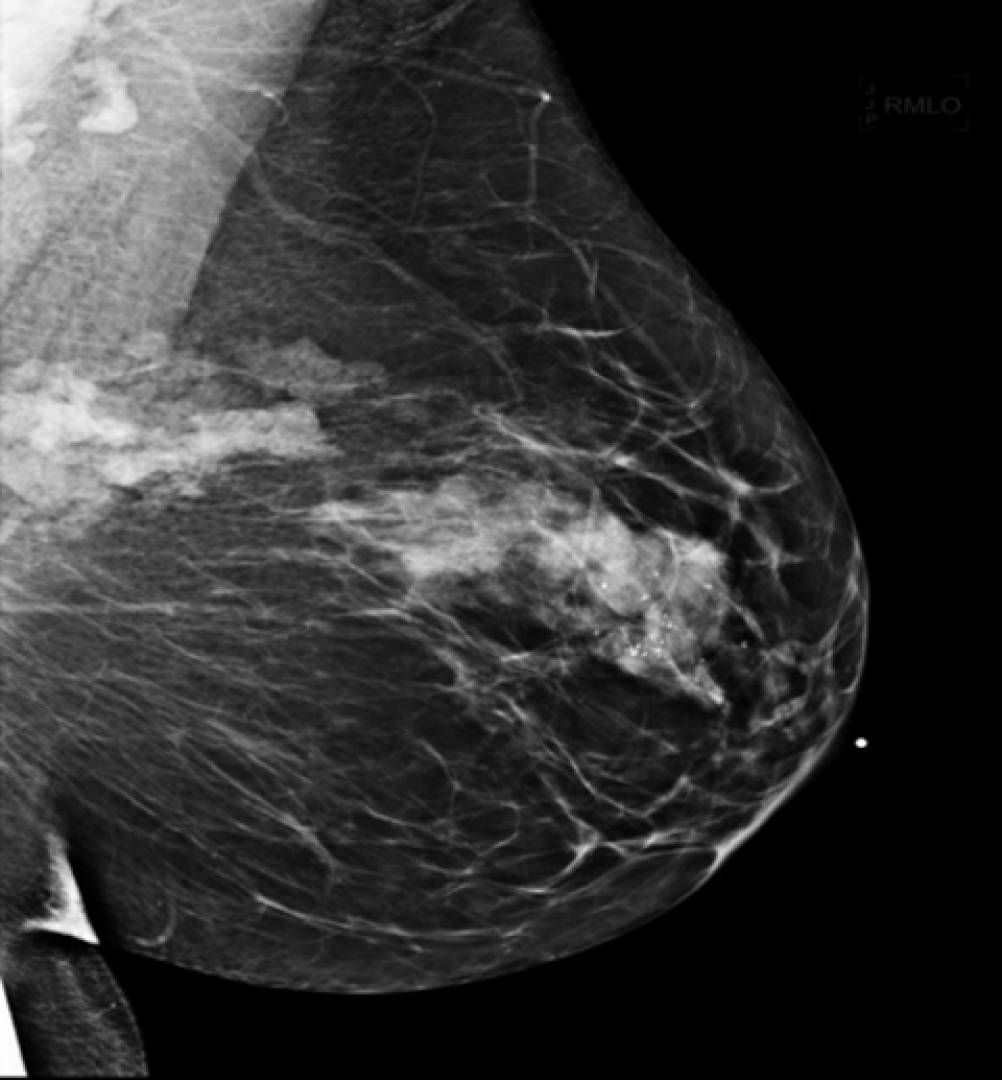

Фиброаденома молочной железы - доброкачественное образование, которое часто встречается у женщин. Оно может быть обнаружено при помощи различных методов диагностики, включая маммографию. Ниже представлены фотографии, помогающие понять, как выглядит данное заболевание.

Злокачественные опухоли молочных желез

Маммография и ее роль в диагностике фиброаденомы молочной железы

Маммография - это рентгенологическое исследование молочных желез. Оно позволяет выявить различные изменения в тканях, включая фиброаденому. На маммограммах можно увидеть структурные особенности опухоли и отследить ее динамику во времени.